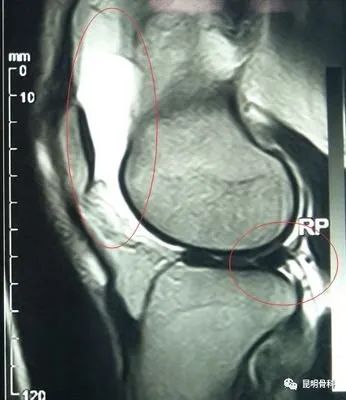

帶您了解膝關(guān)節(jié)滑膜炎

膝關(guān)節(jié)滑膜炎是我們?nèi)粘I钪谐R姷囊环N疾病,引起膝關(guān)節(jié)滑膜炎的原因有很多,比如創(chuàng)傷、感染等等,但最常見病因是創(chuàng)傷。

創(chuàng)傷性膝關(guān)節(jié)滑膜炎,是因為膝關(guān)節(jié)受到急性或慢性外力,造成滑膜損傷,引起滑膜充血、腫脹、膝關(guān)節(jié)腔積液。這種情況多因膝關(guān)節(jié)慢性、反復(fù)勞損、劇烈運動、超負荷運動等引起。目前門診接診很多因參加健步走出現(xiàn)膝關(guān)節(jié)腫脹疼痛患者,就是因為慢性反復(fù)勞損引起的,所以我們要根據(jù)自身情況適當鍛煉。

首先建議做膝關(guān)節(jié)核磁共振檢查,一般情況需要臥床休息,下肢抬高,必要時給予下肢支具外固定。膝關(guān)節(jié)腔積液較多時,可行關(guān)節(jié)穿刺抽液,并關(guān)節(jié)注射藥物,能夠快速緩解關(guān)節(jié)腫脹疼痛,口服非甾體類消炎鎮(zhèn)痛藥物,膝關(guān)節(jié)局部進行膏藥外敷、理療等。